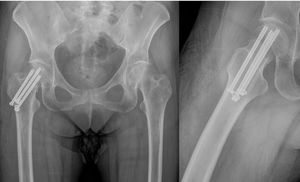

The remaining variables did not show significant differences (CT vs. FNS): avascular necrosis of the femoral head (Fig. 3) (0% vs. 11.1%; p=.391); Femoral neck nonunion (0% vs. 20%; p=.163); residual groin pain (42.9% vs. 37.5%, p=.98); complete joint balance (85.7% vs. 87.5%, p=.98); blood loss or difference (measured in haemoglobin levels g/dL) before and after surgery (median 1.6g/dL vs. median 1.2g/dL; p=.571); and presence of femoral neck shortening on follow-up radiographs (7.1% vs. 11.1%; p=1).